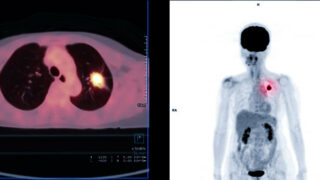

PET検査 PET画像で濃く表示される部分はがん? PET検査の結果の見方、見つかりやすい病気、併用検査について解説 人間ドックでPET検査を受けると、多くの場合、検査結果とともに画像が送られてきます。画像に色調が濃... 公開日: 2023.03.28 更新日: 2023.04.03

PET検査 PET検査はがん以外の病気にも反応。炎症や良性疾患によるケース、認知症を早期発見するためのPETも紹介 人間ドックとしてのPET検査は、ほぼ全身のがんの早期発見を目的として用いられる検査で、がん細胞に薬... 公開日: 2023.03.23

PET検査 【がん検査】PET検査とは? 費用、保険適用の要件、注意点をわかりやすく解説 PET検査はほぼ全身のがんを1回で調べるのに優れた検査で、全身のがんが心配な方、どこを重点的に調べ... 公開日: 2022.03.14 更新日: 2026.02.12

PET検査 PET-CTとPETの違い-費用や医療施設選びのポイントなども解説 PET-CT検査は、全身のがんを一度でスクリーニングできるため、早期発見・早期治療に役立ちます。た... 公開日: 2021.03.31 更新日: 2026.01.26